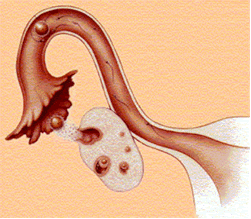

1. Ovarios

1. Luteoma del embarazo

1. Quistes de la teca luteínica

2. Trompas de Falopio